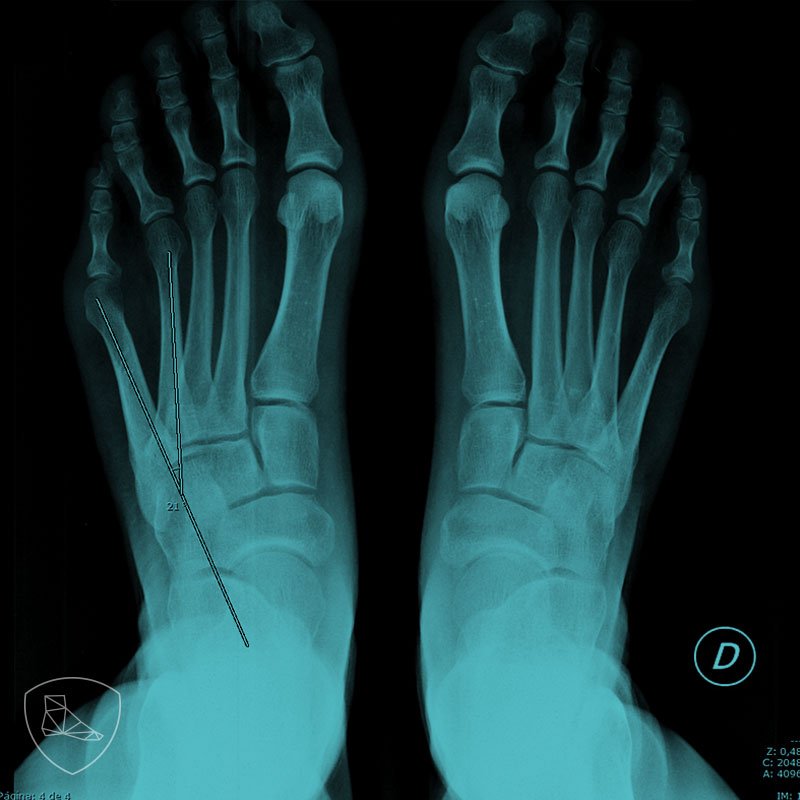

From www.semanticscholar.org

Figure 2 from Patología del quinto radio. Parte III Quintus Varus Quintus Varus Definition Bunionette deformities, commonly called tailor's bunion, are prominences on the lateral aspect of the 5th metatarsal head. The bunionette, also known as quintus varus or tailor’s bunion, is a toe deformity caused by a deformation of the 5th metatarsal bone. Most commonly referred to as overlapping or overriding fifth toe, crossover toe, or digiti quinti varus is a congenital deformity. Quintus Varus Definition.